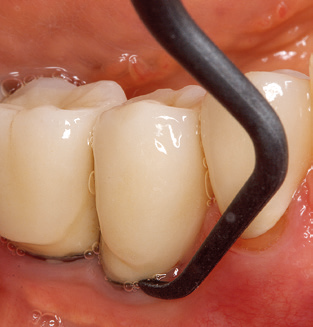

Of course, working tips for the cleaning of implant surfaces are also indispensable for SPT in patients fitted with implants. The implant cleaning attachment on the system used here is characterised by its tapered, hexagonal design. This design allows light, atraumatic penetration of the peri-implant pocket and displays a good cleaning performance (Fig. 7).

Following machine cleaning of the tooth and implant surfaces, the surfaces of the natural teeth are cleaned manually using standard hand instruments. When performing manual cleaning, particular attention must be given to maintaining the correct angle of application, appropriate sharpness, good support and working with the curette from apical to coronal. Either titanium or carbon curettes should be used for post-cleaning of the implant structures (Fig. 8). In addition to the use of ultrasonic devices, power jet devices can also be used in conservative dentistry. However, it must be taken into consideration that these procedures are not suitable for removing hard deposits and thus they cannot replace the use of hand instruments and ultrasonic instruments completely. In all cases, cleaning is followed by mechanical polishing of the accessible tooth and implant surfaces with polishing cups and polishing compounds (Fig. 9).

Fig. 4: Flexible probes with millimetre markings are recommended for the probing of dental implants (e.g. Colorvue Kit PCV11KIT6, Hu­Friedy). – Fig. 5a and b: A straight working tip (1P, W&H Dentalwerk Bürmoos GmbH) is a suitable instrument for use on all natural teeth. – Fig. 6: Curved working tips (3Pr/3Pl, W&H Dentalwerk Bürmoos GmbH) lend themselves to the processing of difficult-to-reach areas of the tooth and root surfaces (e.g. furcations). – Fig. 7: The tapered, hexagonal implant cleaning tip (1I, W&H Dentalwerk Bürmoos GmbH) permits atraumatic and efficient cleaning of the crown and abutment surfaces. – Fig. 8: Titanium and carbon curettes are suitable instruments for the manual cleaning of the implant surfaces.